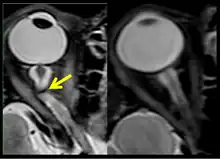

The fourth case of visual changes on orbit was significant for a history of transsphenoidal hypophysectomy for macroadenoma where postoperative imaging showed no residual or recurrent disease. Approximately 2 months into the ISS mission, the astronaut noticed a progressive decrease in near-visual acuity in his right eye and a scotoma in his right temporal field of vision.[5]

Figure 10: MRI (R+30 days) of the fourth case of visual changes from long-duration spaceflight. There is prominence of central T2-hyperintensity of the optic nerves bilaterally, right greater than left approximately 10 to 12 mm posterior to the globe (arrow) that represents an element of optic nerve congestion.

Figure 11: MRI (R+30 days) of the fourth case of visual changes from long-duration spaceflight. Tortuous optic nerve and kink on left (arrow). Control orbit on the right.

During the same mission, another ISS long-duration astronaut reported the fifth case of decreased near-visual acuity after 3 weeks of spaceflight. In both cases, CO2, cabin pressure and oxygen levels were reported to be within acceptable limits and the astronauts were not exposed to any toxic fumes.[5]